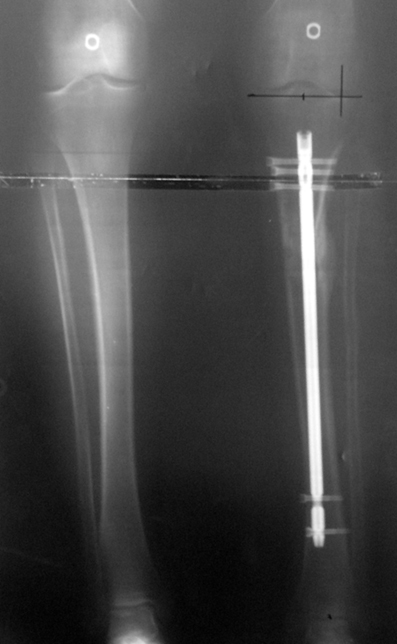

3. POSTTRAUMATIC LOWER LIMB SHORTNESS (MALUNION)

This type of shortness occurs after a fracture heals in a shortened position. Most cases are seen in adults and can be treated with one lengthening operation. Additional deformities can be corrected simultaneously. Most of these cases can be treated with lengthening over nail or just corrections and intramedullary nailing.